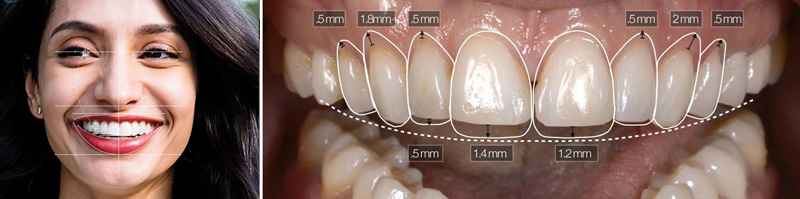

Es una especialidad que se ocupa de la prevención y el tratamiento de las irregularidades de la posición de los dientes y los huesos maxilares (maxilar superior y mandíbula), llevándolos a una posición correcta desde el punto de vista funcional y estético.

La respuesta es SI. La maloclusión (incorrecta alineación de los dientes) puede tener impacto tanto en comer como en hablar, además de hacer más probable que te lastimes los dientes o la mandíbula. Un buen engranaje dental te ayudará a prevenir dolores y molestias en los músculos y articulaciones mandibulares (pacientes con bruxismo). Además, en muchas ocasiones la ortodoncia es la mejor opción antes de emprender tratamientos invasivos, o una rehabilitación con prótesis dentales que pueden llegar a desgastar tus dientes. Sin mencionar la mejoría en lo que se refiere a la limpieza, problemas periodontales, mejoría en la oclusión, y por consiguiente en la masticación, dolores cervicales, migrañas por tensión muscular, etc.

¿Cuáles son los beneficios de utilizar ortodoncia?

• MEJOR: autoestima, estética facial y dental, limpieza, masticación, armonía entre los dientes y la estabilidad de la articulación temporomandibular (ATM)

• MENOS: riesgo de caries, riesgo de enfermedad periodontal, sensibilidad dental, desgaste en los dientes, bruxismo, movilidad dentaria, impotencia funcional en la masticación, dolor muscular en músculos faciales y del cuello